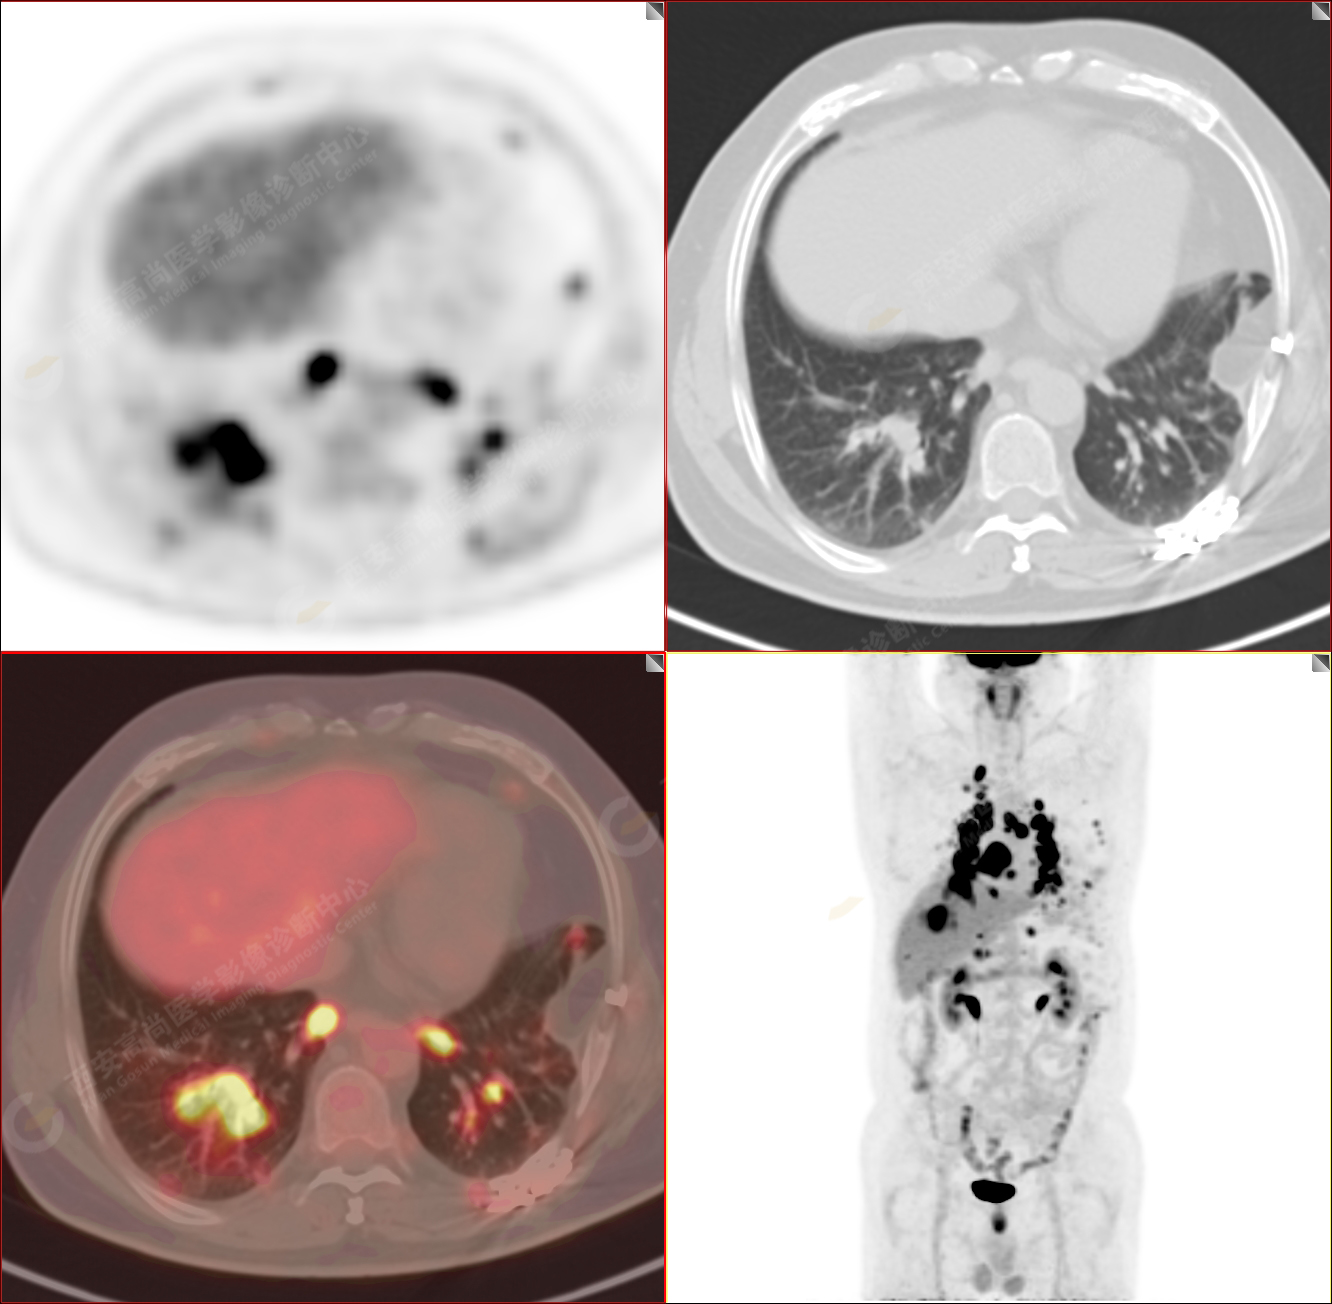

PET/CT圖像